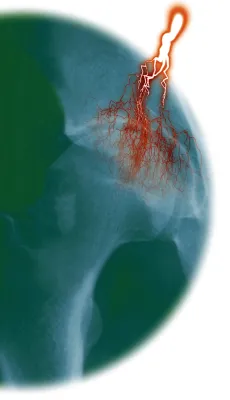

Die Gelenksarthrose (Osteoarthritis) ist eine schmerzhafte Abnützungserscheinung in den Knie- Hüft- oder Fingergelenken und betrifft etwas mehr Frauen als Männer. Bei dieser heute häufigsten Erkrankung des Bewegungsapparates kommt es am Gelenk zunächst zu einer Verschmälerung und Auffaserung der Knorpelschicht, später zu einem fortschreitenden Knorpelverlust. In späten Stadien einer Arthrose reibt dann Knochen auf Knochen. Die degenerativen strukturellen Schädigungen des Gelenkknorpels können auch auf Knochen und Gelenkkapsel übergreifen. Typisch für ein arthrotisches Gelenk ist die messbare Konzentration entzündungsauslösender Zytokine, durch die mehr Knorpel abgebaut wird, als der Körper neu erzeugen kann. Der Knorpel im Gelenk dient jedoch als Gleitschicht – ist er beschädigt oder vermindert, ist die Beweglichkeit des Gelenks schmerzhaft eingeschränkt.